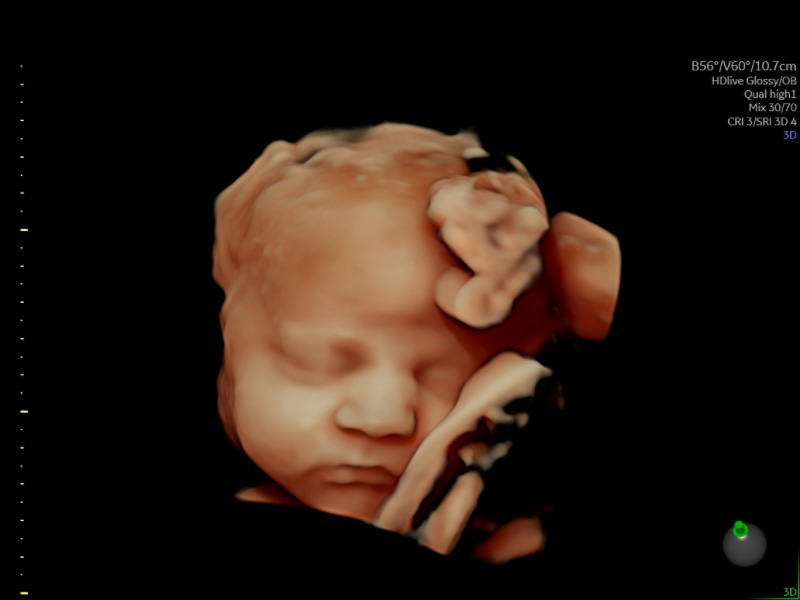

HerView Premium 3D/4D/HD Growth and Wellbeing Scan (22-34 Weeks)

The HerView Premium 3D/4D/HD Pregnancy Scan offers an unforgettable opportunity to witness your baby’s development in exceptional detail. Ideally carried out between 22 and 34 weeks, this scan allows you to see your baby’s features, movements, and tiny expressions through advanced 3D, 4D, and HD imaging. Our clinical specialist sonographers…